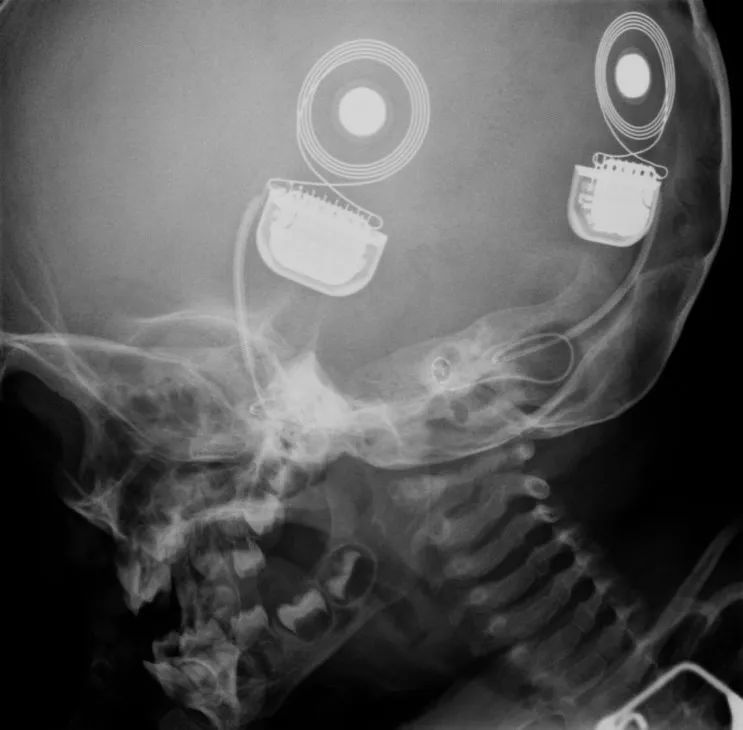

双耳植入人工耳蜗者的X光|MED-EL